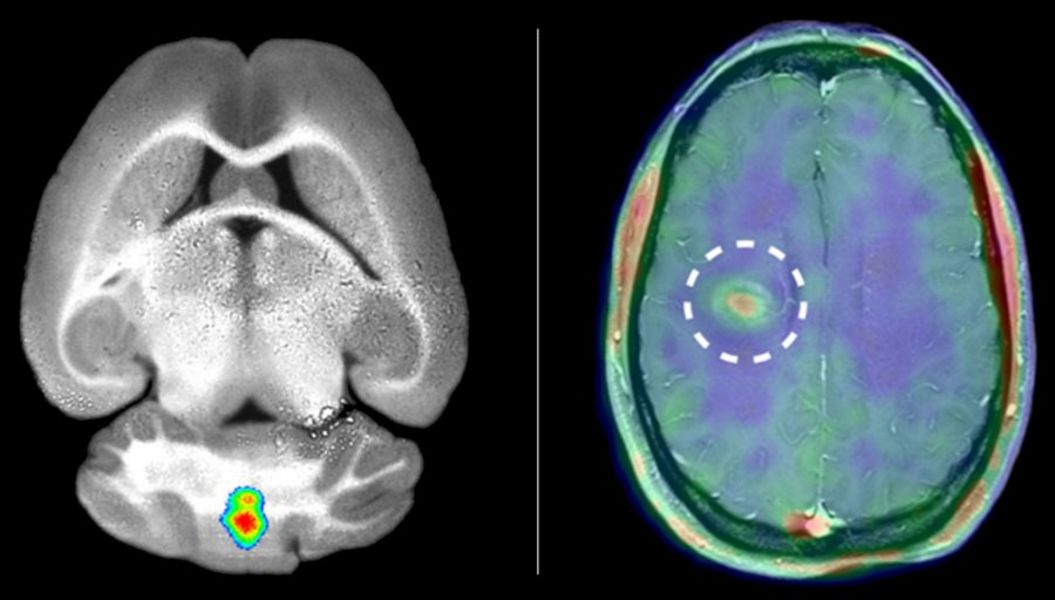

In ersten Untersuchungen gelang es den Wissenschaftlern, das Verfahren auf den Menschen zu übertragen. Da die Lichtsignale des fluoreszierenden Tracers die dickeren Gewebeschichten beim Menschen nicht durchdringen können, wandelten die Forscher den Tracer um und hängten statt des Fluoreszenz-Farbstoffs einen radioaktiven Signalgeber an. Dessen Strahlung lässt sich mit einem speziellen Verfahren, der Positronen-Emissions-Tomographie (PET), messen und sichtbar machen. Nuklearmediziner und Neurologen des münsterschen Exzellenzclusters, die gleichzeitig am Universitätsklinikum tätig sind, führten nun erste Fallstudien bei Patienten mit Multipler Sklerose durch. Das Ergebnis: Bei Patienten mit akutem MS-Schub reicherte sich der Tracer deutlich an, und zwar schon bevor im betroffenen Bereich mit dem traditionellen Verfahren der Magnet-Resonanz-Tomographie eine Schädigung der Blut-Hirn-Schranke zu sehen war.